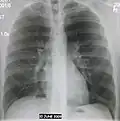

AP CXR showing left lower lobe pneumonia associated with a small left sided pleural effusion -

AP CXR showing right lower lobe pneumonia -

AP CXR showing pneumonia of the lingula of the left lung -